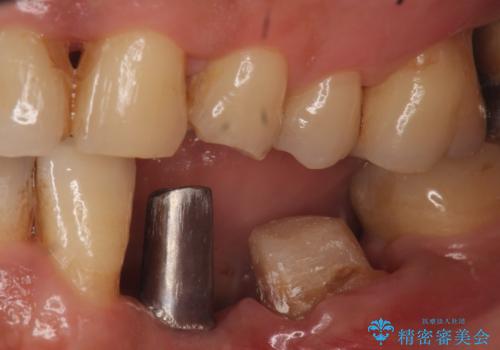

歯列矯正は御希望されなかったため左下4、5番目の歯を抜歯し、インプラントによる欠損補綴を行いました。

ストローマンについて

当院では主にストローマンという種類のインプラントを治療に用いています。

ストローマンは世界的にもNo1のシェアを誇り、骨との適合にも優れたインプラントです。

カスタムアバットメントについて

カスタムアバットメントは患者様それぞれの歯茎に合わせて製作されたオーダーメイドのアバットメントです。

既製のアバットメントに比べ適合がよく、高い清掃性を誇ります。